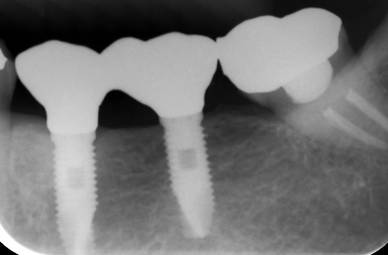

治療後。歯周病で失われた骨が回復しています。使用インプラントはスプラインツイストです。

インプラント装着後6年。順調に経過しています。12か月毎のメインテナンスをしています。

2019年 歯根破折や根面齲蝕のため抜歯した部位をインプラントで補綴しました。ストローマンとスプラインが混在しています。先端の丸井インプラントはストローマンです。

ストローマンインプラントとスプラインインプラントが隣り合わせに埋入されています.このころストローマンからスプラインに変えています。変えた理由は前歯部の審美性に優れていること、アバットメントの自由度があること、抜歯後すぐに埋入できるなどでした。